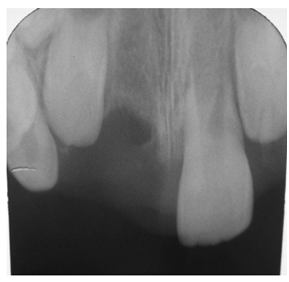

A 10year old boy reported to the department of Pedodontics with a chief complaint of missing upper front tooth and gave a history of fall from bike while 5 days back. They had been to pediatrician for the lacerated lip and got it sutured. Parents had kept the avulsed tooth in paper without knowledge of reimplantation of the same tooth. Patient had no relevant medical and family history. On examination swelling and suture was present on upper lip, lacerated gingiva with healing socket in 11 regions. 21 was intact, vital and non mobile. (Figure 1) (Figure 2) On examination of avulsed tooth 11, it was found to have open apex (Figure 3). On intraoral radiographic examination, no fracture was seen with alveolar bone (Figure 4). Thus avulsed tooth was cleaned and debrided with soft pumice prophylaxis, gentle scaling was done to remove ligament remnants. It was then placed in 1.23% sodium fluoride for 15minutes. Extraoral endodontic therapy was also done using retrograde filling of MTA (Figure 5). Local anesthesia was administered and socket was cleaned, curetted and irrigated to remove clot and debris and 11 was slowly reimplanted in socket. Orthodontic wire – composite splinting was done for 4weeks as the dry storage was more than 60minutes (Figure 6). Systemic antibiotics amoxicillin and doxycycline were prescribed for 5days. The patient was recalled after 1 month and splint was removed. No mobility was present. Again patient was recalled after 2months to check the condition (Figure 7). Again patient was recalled after 6months; tooth had slightly discolored but was not mobile and maintained the space (Figure 8). Patient was happy and contended with the reimplantation of his own tooth without disturbing his original look.

Figure 4 Preoperative radiograph.

Figure 5 Intraoperative radiograph showing 11 with MTA retrograde obturation.